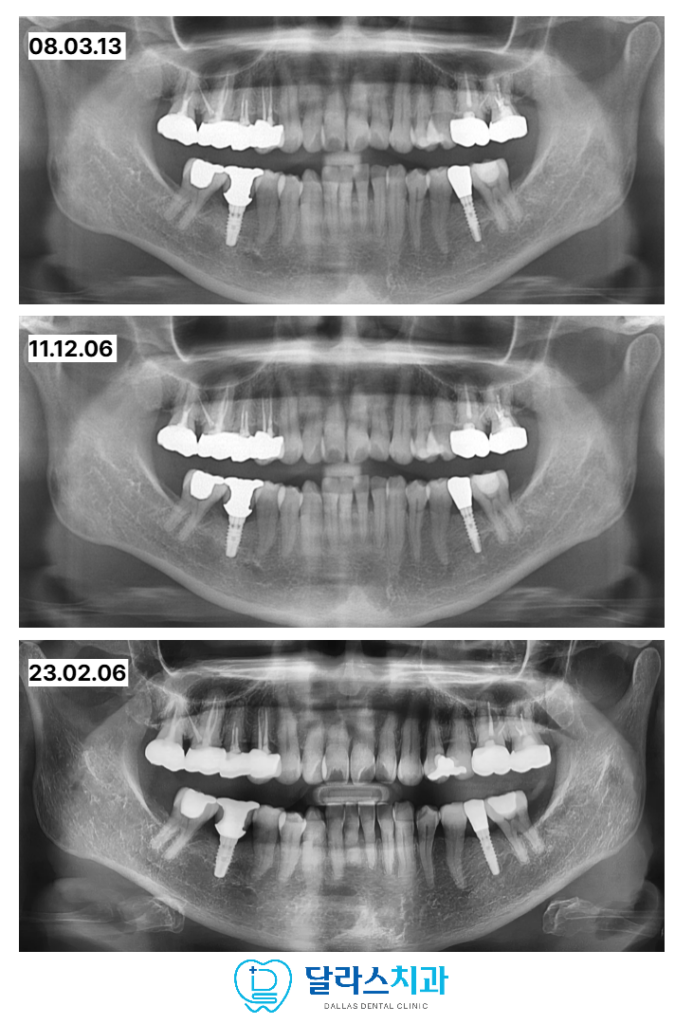

먼저 치아 이동을 위한 공간을 확보하기 위해

더 이상 기능하지 않는 사랑니를 발치하였습니다.

그 다음 쓰러져 있던 47번 어금니를 올바른 각도로 세우기 위해

교정용 나사인 스크류를 지지대로 활용하여

어금니를 바로세우는 업라이팅 치료를 진행하였습니다.

기울어진 치아를 수직으로 바로 세움으로써 임플란트가 들어갈 공간을 마련하고

무너졌던 씹는 평면의 높이를 정상화하였습니다.

이렇게 기초 토대를 견고히 다진 뒤에 비로소 적절한 위치에 임플란트를 식립하였습니다.

이러한 정교한 수술과 보강 과정을 거친 결과

노원치과 환자분은 08년도 이후 15년이 지난 최근까지도

아무런 불편함 없이 임플란트를 사용하고 계십니다.